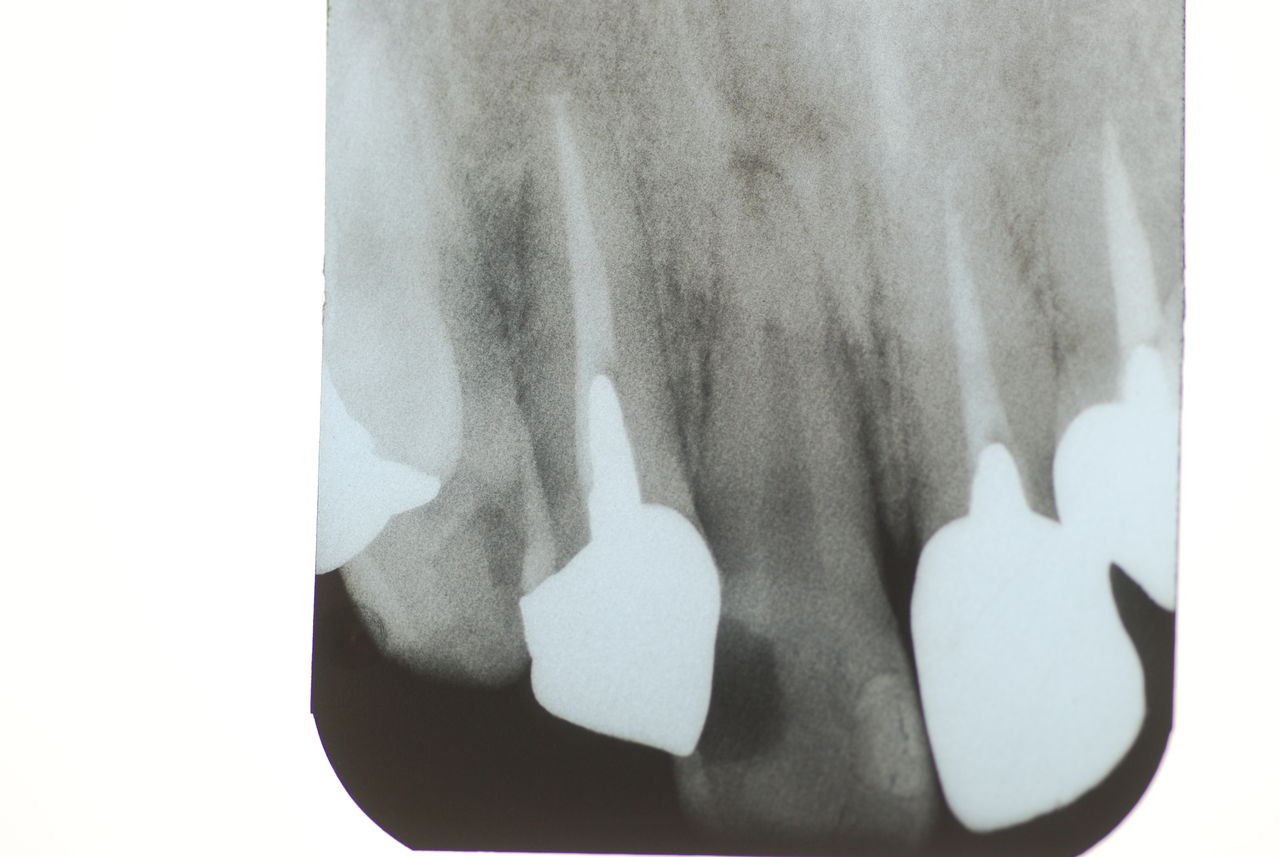

歯周病の疑いで東京のかなり遠方の方が来院されました。

驚くべきことですが、定期検診は受けていたそうです。しかしながら歯周病の指摘は受けたことがないそうです。

何故か?定期検診が虫歯のチェックのみになり、又肝心の歯周病の検査や歯周病の部分の予防や治療のためのブラシの使い方などを学んだ事がないのです。

本当に患者さんのことを考えると憂鬱になります。歯周病が悪化すると殆ど回復は無理だからです。